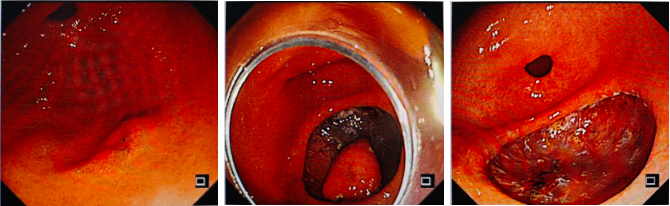

胃竇前壁一凹陷小病灶,病理活檢重度異型增生

胃竇前壁的凹陷小病灶,病理活檢提示重度異型增生(癌前病變),通過 ESD 技術順利切除,阻斷癌變進程;